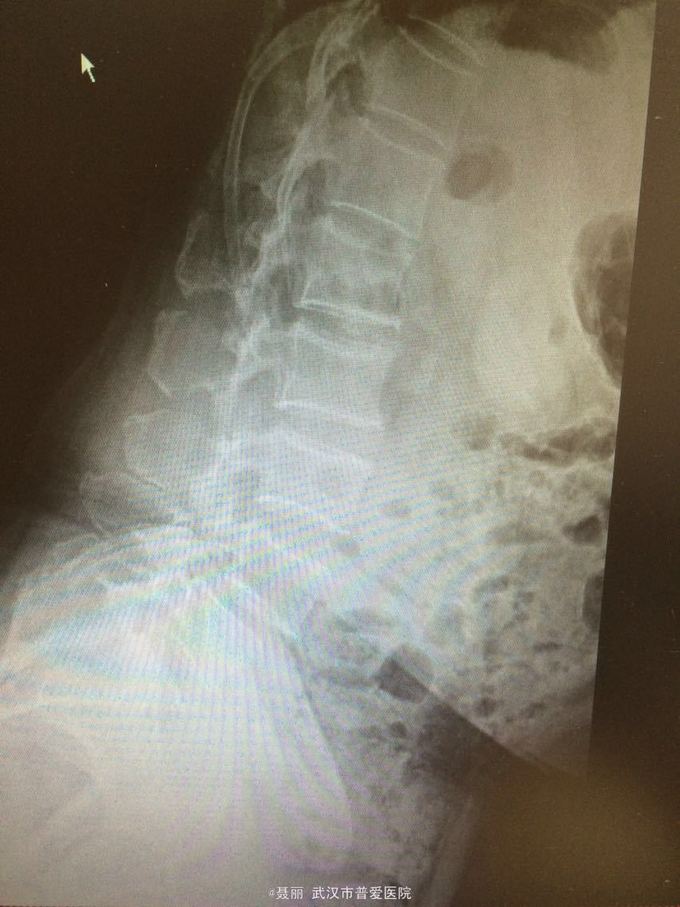

患者,女,61岁 因腰部疼痛,伴左下肢酸胀、疼痛、麻木5月余入院。 患者约5月前无明显外伤等诱因感腰腿疼痛不适,以腰部及左下肢为主,活动后左下肢疼痛加重,休息可缓解。 既往病史:既往体健,否认高血压、糖尿病等其他传染病史,否认食物药物过敏史。

辅助检查:2015年2月27号到我院拍腰椎MRI检查提示:L4椎体Ⅰ-Ⅱ度滑脱,腰椎退变。

初步诊断:腰椎滑脱症 治疗计划:1、完善相关检查:胸片、心电图,血常规,尿常规,肝肾功能电解质、术前全套 2,活血化瘀扩管治疗。卧床休息。 L4滑脱复位+L4/5椎间盘摘除、椎管减压+椎间cage3植骨融合术

:平卧位休息,加强双下肢主,被动活动,加强直腿抬高锻炼及腰背肌锻炼。2.可佩戴腰部支具逐步下地活动 ,避免弯腰负重,服用营养神经药物治疗,一个月后复查 恢复良好